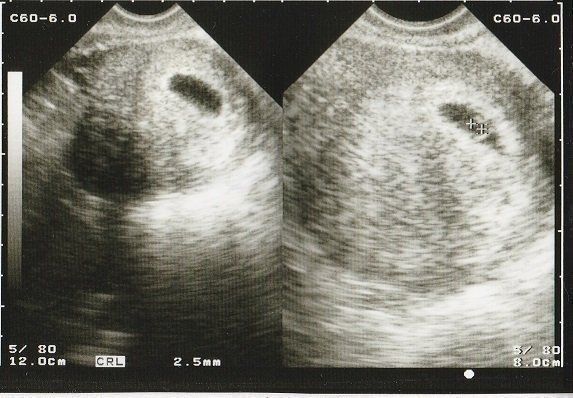

ママにエールさんの妊娠6週目のエコー写真

薄茶色のおりもの(出血)があり、気になって産院へ電話。「とりあえず、診察へ」と言われて受診しましたが、妊娠初期によくある程度の出血だから大丈夫とのこと。出血止めの薬だけ処方されました。ちょうどこの時、エコーで白い小さな粒を確認。「これが赤ちゃんに成長していきます」と先生に聞いて、愛しさでエコー写真をしばらく眺めていました。夫に見せたら、「ちっこい」と笑っていました。